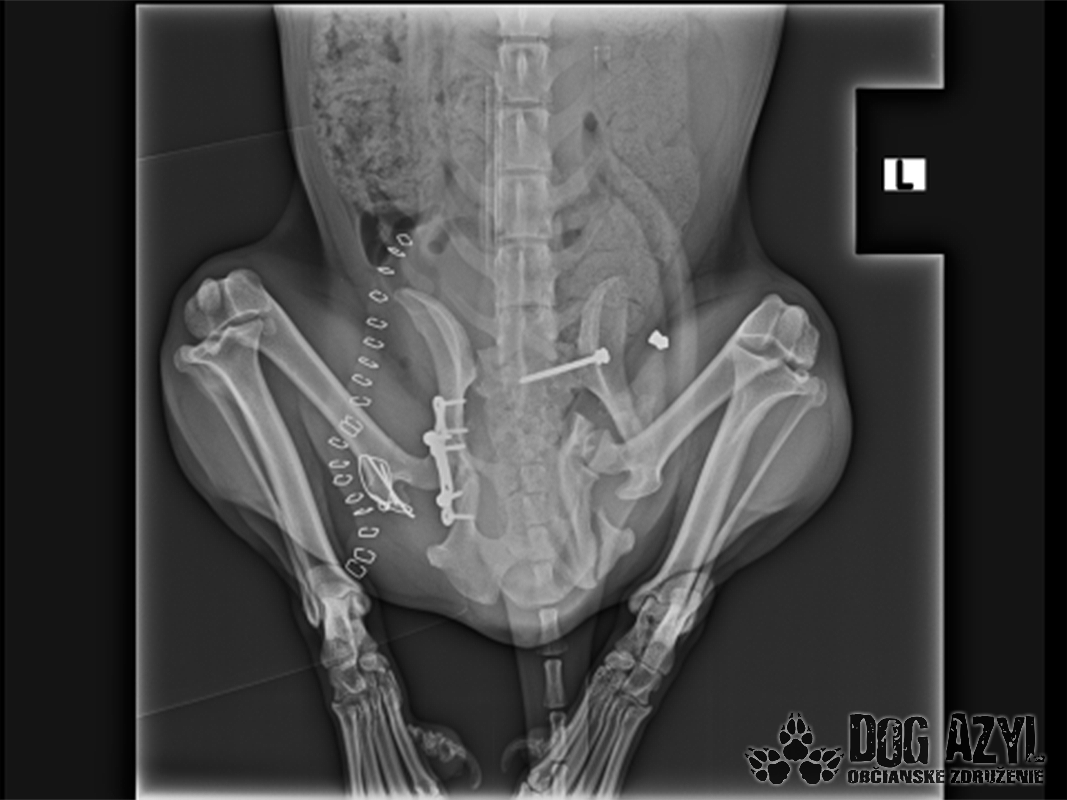

Vianoce nám klopú na dvere a mali by to byť sviatky radosti a pokoja. No u nás nebudú a pre malého Jamesa už vôbec nie. Malého Jamesa sme prijali s mnohonásobnými fraktúrami panvy. Presnejšie, s obojstrannou iliosakrálnou luxáciou/fraktúrou, viacnásobnou fraktúrou panvy, vrátane fraktúry kranialneho acetabula obojstranne. Áno, znie to hrozivo a keď si pozriete snímky z RTG, bude to ešte hrozivejšie (ďalšie snímky ešte doplníme).

Čakali ho teda štyri, veľmi náročné ortopedické operácie, takže sa musel trocha posilniť. Do starostlivosti si ho vzala MVDr. Panyi Terzieva a 17.11. mohol absolvovať prvú operáciu. V "prvom kole" krpec zvládal anestézu tak dobre, že sa rovno mohli spojiť dve operácie a tak sa celá ľavá strana dala do poriadku. Zostal samozrejme naďalej hospitalizovaný. Ďalší zákrok sa naplánoval na 20.11. a našťastie opäť všetko prebehlo hladko, a zoperovala sa celá pravá strana(nechceme sa dlho rozpisovať, prikladáme lekársku správu). James bol prepustený 24.11. ako chodiaci pacient a bez problémov ovládal aj vylučovanie! Je to priam zázrak, za ktorý opäť vďačíme MVDr. Vatolíkovi a jeho teamu.